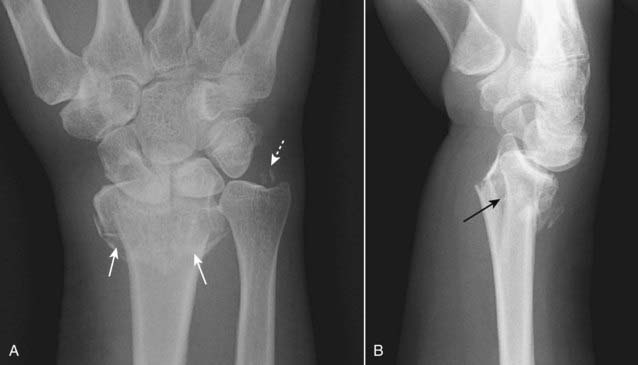

Figure 22-21 Colles’ fracture, frontal (A) and lateral (B) views.

Colles’ fractures are fractures of the distal radius (solid white arrows) with dorsal angulation of the distal radial fracture fragments (solid black arrow) caused by a fall on the outstretched hand (sometimes abbreviated as FOOSH). There is frequently an associated fracture of the ulnar styloid (dotted white arrow).

Figure 22-22 Smith’s fracture.

A Smith fracture is a fracture of the distal radius (solid white arrow) with palmar angulation of the distal radial fracture fragment (solid black arrow), the reverse of a Colles fracture. It is caused by a fall on the back of the flexed hand.